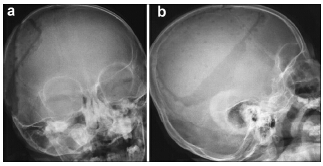

摘要 Objective: To evaluate the clinical results of repairing skull defects with biomimetic bone (nano-hap/collagen composites, NHACs) in children. Methods: Thirteen children with skull defects were treated with NHACs in our hospital. The NHACs molded with the help of a 3D printer were used in the operations. Results: All 13 operations were successful, and patients recovered without infection. Only one patient suffered from subcutaneous hydrops post-operation. The implanted NHACs remained fixed well after 1 year, and their CT HU values raised gradually. Skull shapes of children developed normally. Recovery of neurological and cognitive function was significant. Conclusions: NHAC, chosen to repair skull defects in children, can coexist with normal skull and reduce the negative effects on growth and development. NHAC could be a good choice for children with skull defects.

Abstract: Objective: To evaluate the clinical results of repairing skull defects with biomimetic bone (nano-hap/collagen composites, NHACs) in children. Methods: Thirteen children with skull defects were treated with NHACs in our hospital. The NHACs molded with the help of a 3D printer were used in the operations. Results: All 13 operations were successful, and patients recovered without infection. Only one patient suffered from subcutaneous hydrops post-operation. The implanted NHACs remained fixed well after 1 year, and their CT HU values raised gradually. Skull shapes of children developed normally. Recovery of neurological and cognitive function was significant. Conclusions: NHAC, chosen to repair skull defects in children, can coexist with normal skull and reduce the negative effects on growth and development. NHAC could be a good choice for children with skull defects.